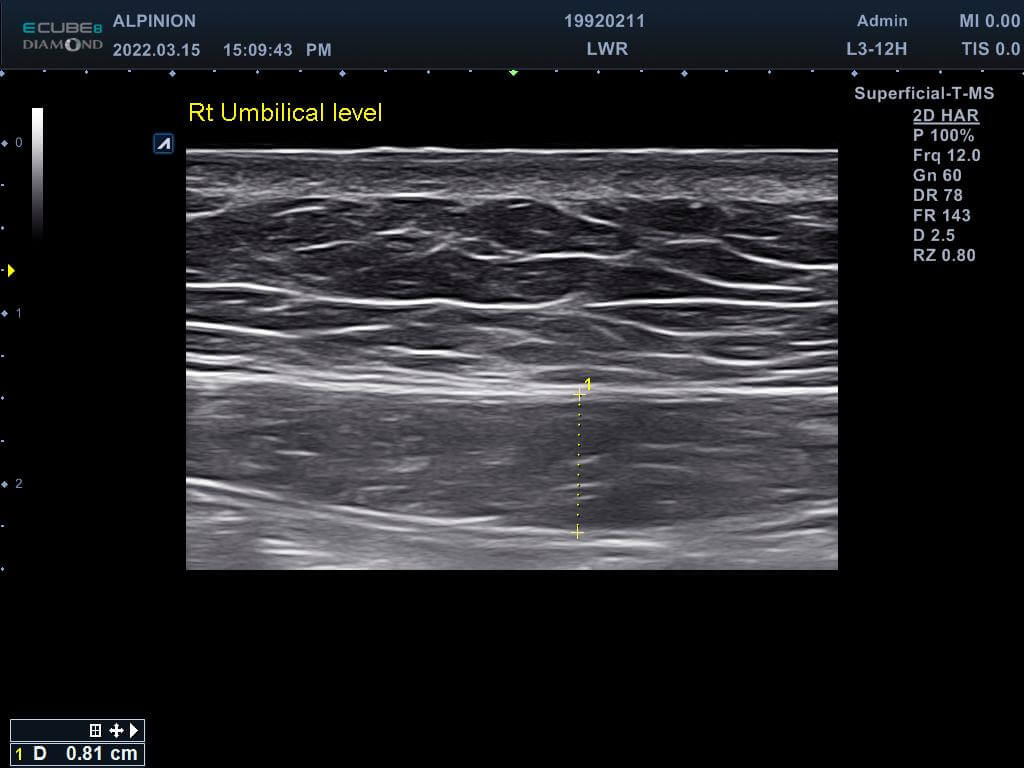

專業的醫師先在磁刺激前測量林小姐的腹直肌厚度,發現雙側的腹直肌分別為0.81cm(右側)與0.78cm(左側),同時雙側白線的距離也長達1.96cm,已經達到腹直肌分離的狀況。在使用了四周共8次的增肌減脂機後,雙側的腹直肌增厚為0.93cm(右側)與0.82cm(左側),同時雙側白線的距離減少1.46cm並明顯增厚,代表結締組織已經增生修復了。

增肌減脂(前)右側肚臍高度腹直肌0.81cm